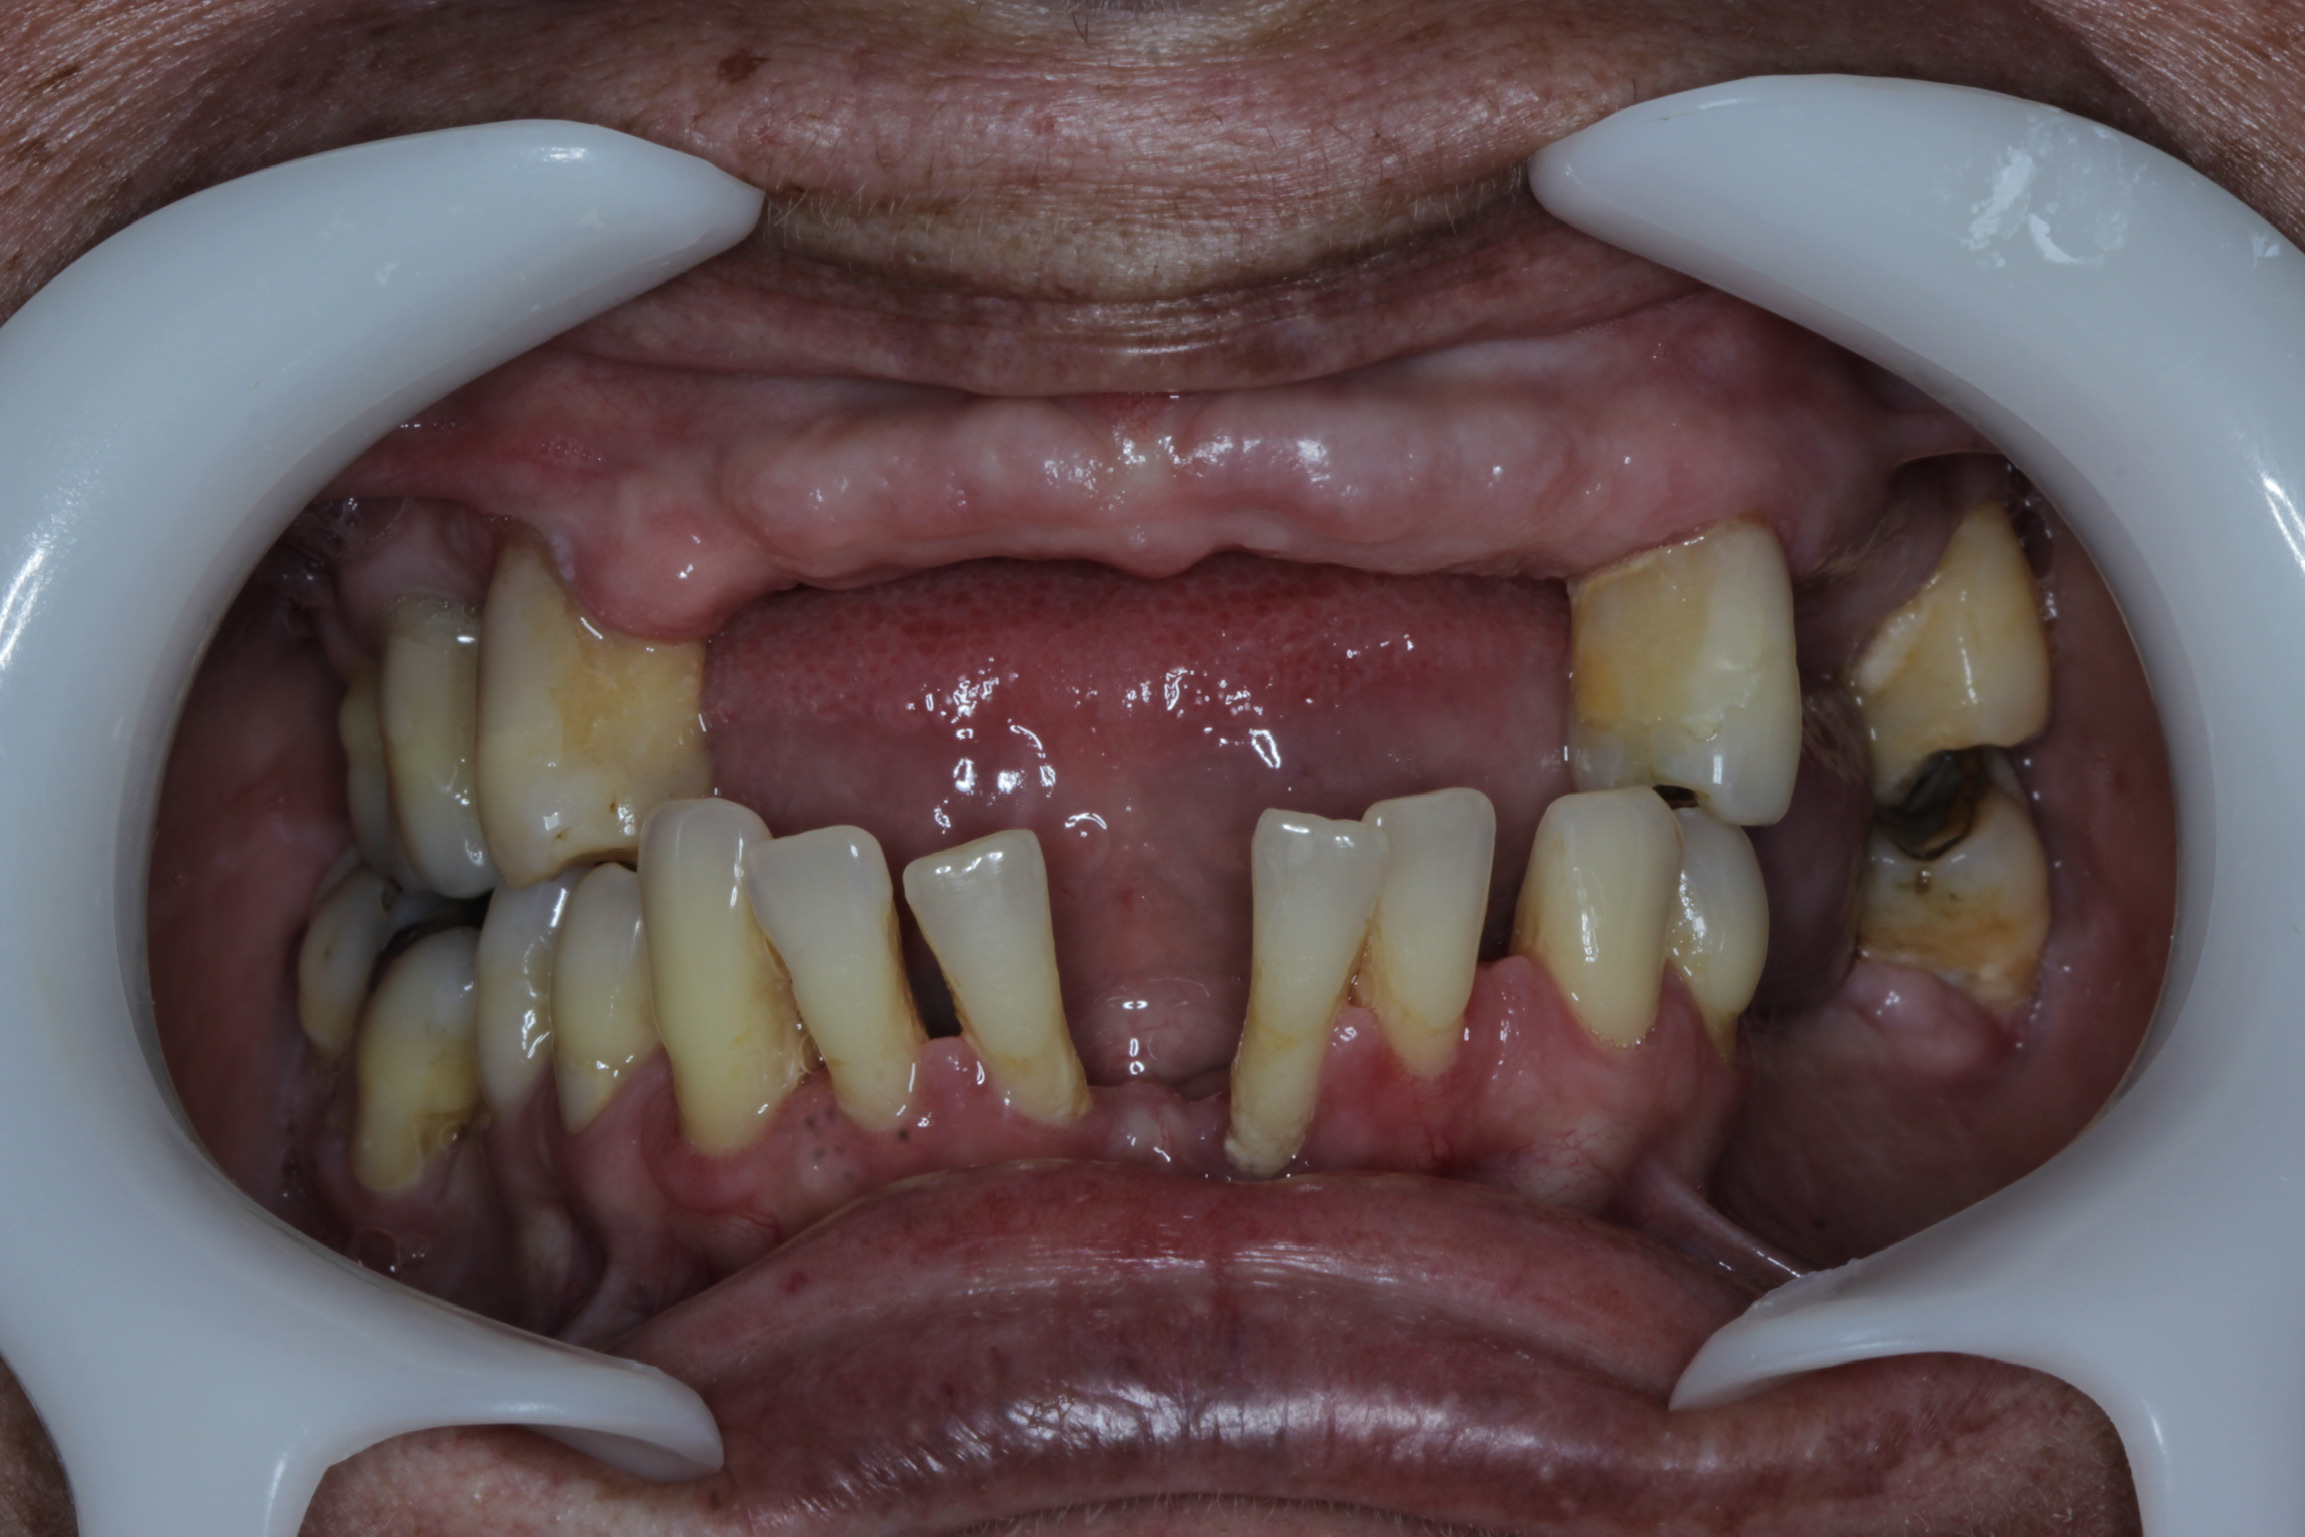

Segundo um estudo realizado por pesquisadores da Universidade Estadual de Campinas (Unicamp), ter uma rotina estressante pode resultar em prejuízos para a saúde bucal. Quem é mais estressado ou sofre de ansiedade crônica tem maiores chances de desenvolver doenças bucais que podem resultar até na perda dos dentes.

Isso ocorre porque o cansaço extremo, falta de sono, nervosismo e ansiedade contribuem para a diminuição do fluxo salivar ou provocam o ranger dos dentes durante o dia e à noite, o que pode causar fraturas graves nos dentes.

• O bruxismo é uma doença caracterizada pelo ranger ou forte pressão nos dentes. De acordo com a Organização Mundial da Saúde (OMS) essa doença atinge cerca de 84 milhões de brasileiros;

• A periodontite consiste em uma inflamação ou infecção crônica que atinge os tecidos que estão ao redor do dente e que o sustenta.

Essas doenças são tratáveis e podem até ser curadas através do diagnóstico precoce. Com a avaliação de um dentista é possível descobrir o estágio da doença e quais serão os procedimentos necessários, variando de paciente para paciente. Em caso de perda dos dentes, a reabilitação por meio do uso de implantes é o mais recomendável.